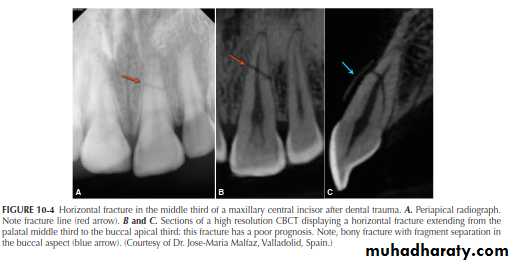

A major advantage of CBCT is the visualization of anatomic

structures in three planes, generally referred to as coronal, axial (transverse), and sagittal reconstructions. CBCT technology also allows for panoramic and oblique reconstructions in addition to anatomic-specific reformatting such as temporomandibular joint (TMJ) improved the sensitivity and specificity of accurately detecting lesions or conditions affecting the jaws